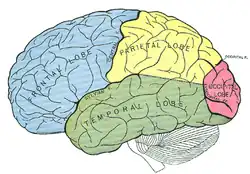

O cérebro humano é o órgão central do sistema nervoso humano e, com a medula espinhal, forma o sistema nervoso central. O encéfalo consiste no cérebro, no tronco cerebral e no cerebelo. O cérebro controla a maioria das atividades do corpo, ao mesmo tempo em que processa, integra e coordena as informações que recebe do sistema sensorial e toma decisões quanto às instruções enviadas ao resto do corpo. O órgão, que está contido e protegido pelos ossos do crânio da cabeça e é a maior parte do encéfalo humano, consiste em dois hemisférios cerebrais. Cada hemisfério possui um núcleo interno composto de matéria branca e uma superfície externa - o córtex cerebral - composto de matéria cinzenta. O córtex tem uma camada externa, o neocórtex e um alocórtex interno. O neocórtex é formado por seis camadas neuronais, enquanto o alocórtex tem três ou quatro. Cada hemisfério é convencionalmente dividido em quatro lobos cerebrais - frontal, temporal, parietal e occipital. O lobo frontal está associado às funções executivas, como autocontrole, planejamento, raciocínio e pensamento abstrato, enquanto o lobo occipital é dedicado à visão. Dentro de cada lobo, áreas corticais estão associadas a funções específicas, como as regiões sensoriais, motoras e de associação. Embora os hemisférios esquerdo e direito sejam bastante semelhantes em forma e função, algumas funções estão associadas especificamente a um lado, como a linguagem à esquerda e a habilidade visual-espacial à direita. Os hemisférios são conectados por tratos nervosos comissurais, sendo o maior o corpo caloso.

Embora até há poucos anos se pensasse que a função das células de Glia é essencialmente a de nutrir, isolar e proteger os neurônios, estudos mais recentes sugerem que os astrócitos podem ser tão críticos para certas funções corticais quanto os neurônios. As diferentes partes do córtex cerebral são divididas em quatro áreas chamadas de lobos cerebrais, tendo cada uma funções diferenciadas e especializadas. Os lobos cerebrais são designados pelos nomes dos ossos cranianos nas suas proximidades e que os recobrem. O lobo frontal fica localizado na região da testa; o lobo occipital, na região da nuca; o lobo parietal, na parte superior central da cabeça; e os lobos temporais, nas regiões laterais da cabeça, por cima das orelhas.

Lobos cerebrais

Os lobos parietais, temporais e occipitais estão envolvidos na produção das percepções resultantes daquilo que os nossos órgãos sensoriais detectam no meio exterior e da informação que fornecem sobre a posição e relação com objetos exteriores das diferentes partes do nosso corpo.

O lobo frontal, que inclui o córtex motor e pré-motor e o córtex pré-frontal, está envolvido no planejamento de ações e movimento, assim como no pensamento abstrato. A atividade no lobo frontal aumenta nas pessoas normais somente quando temos que executar uma tarefa difícil em que temos que descobrir uma sequência de ações que minimize o número de manipulações necessárias. A parte da frente do lobo frontal, o córtex pré-frontal, tem que ver com estratégia: decidir que sequências de movimento ativar e em que ordem e avaliar o seu resultado. As suas funções parecem incluir o pensamento abstrato e criativo, a fluência do pensamento e da linguagem, respostas afetivas e capacidade para ligações emocionais, julgamento social, vontade e determinação para ação e atenção seletiva. Traumas no córtex pré-frontal fazem com que uma pessoa fique presa obstinadamente a estratégias que não funcionam ou que não consigam desenvolver uma sequência de ações correta.

O lobo occipital está localizado na parte póstero-inferior do cérebro. Coberta pelo córtex cerebral, esta área é também designada por córtex visual, porque processa os estímulos visuais. É constituída por várias subáreas que processam os dados visuais recebidos do exterior depois de terem passado pelo tálamo: há zonas especializadas em processar a visão da cor, do movimento, da profundidade, da distância, etc. Depois de percebidas por esta área - área visual primária - estes dados passam para a área visual secundária. É aqui que a informação recebida é comparada com os dados anteriores que permite, por exemplo, identificar um cão, um automóvel, uma caneta. A área visual comunica com outras áreas do cérebro que dão significado ao que vemos tendo em conta a nossa experiência passada, as nossas expectativas. Por isso é que o mesmo objeto não é percepcionado da mesma forma por diferentes sujeitos. Para além disso, muitas vezes o cérebro é orientado para discriminar estímulos. Uma lesão nesta área provoca agnosia, que consiste na impossibilidade de reconhecer objetos, palavras e, em alguns casos, os rostos de pessoas conhecidas ou de familiares

O lobo temporal está localizado na zona por cima das orelhas tendo como principal função processar os estímulos auditivos. Os sons produzem-se quando a área auditiva primária é estimulada. Tal como nos lobos occipitais, é uma área de associação - área auditiva secundária - que recebe os dados e que, em interação com outras zonas do cérebro, lhes atribui um significado permitindo que a pessoa reconheça o que ouve.

O lobo parietal, localizado na parte superior do cérebro, é constituído por duas subdivisões - a anterior e a posterior. A zona anterior designa-se por córtex somatossensorial e tem por função possibilitar a recepção de sensações, como o tato, a dor e a temperatura do corpo. Nesta área primária, que é responsável por receber os estímulos que têm origem no ambiente, estão representadas todas as áreas do corpo. São as zonas mais sensíveis que ocupam mais espaço nesta área, porque têm mais dados para interpretar. Os lábios, a língua e a garganta recebem um grande número de estímulos, precisando, por isso, de uma maior área. A área posterior dos lobos parietais é uma área secundária que analisa, interpreta e integra as informações recebidas pela área anterior ou primária, permitindo-nos a localização do nosso corpo no espaço, o reconhecimento dos objetos através do tato, etc.

A Área de Wernicke é na zona onde convergem os lobos occipital, temporal e parietal que se localiza a área de Wernicke, que desempenha um papel muito importante na produção de discurso. É esta área que nos permite compreender o que os outros dizem e que nos faculta a possibilidade de organizarmos as palavras sintaticamente corretas.